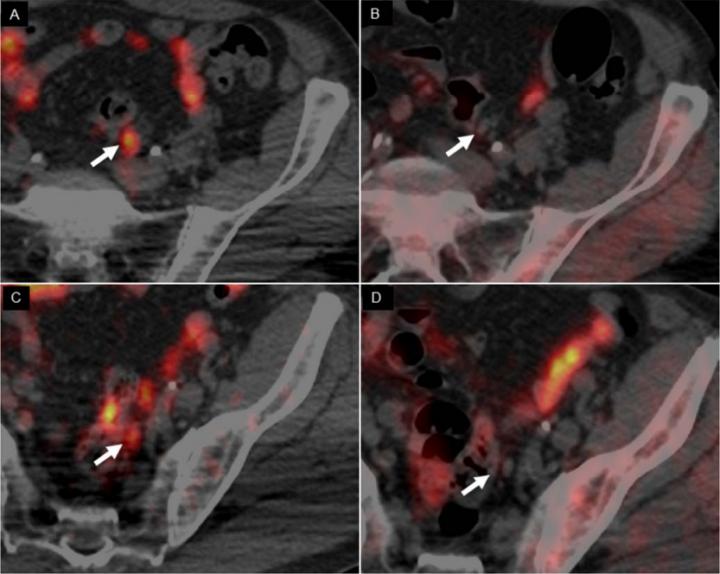

image: In scans of a 62-yr-old man with Gleason 4+3 PCa treated with radical prostatectomy, with rising PSA level (1.32) and PSA doubling time of 3.7 months, 64CuCl2-PET/CT images revealed 2 positive small left iliac lymph nodes (A,C), whereas 18F-Choline PET/CT (B,D) was negative (arrows).

Copper tends to be more concentrated in tumors, making it a good imaging biomarker. For this study of 50 patients, researchers conducted PET/CT scans comparing the new imaging agent, copper-64 chloride (64CuCl2), with fluorine-18-choline (18F-Choline). Multiparametric magnetic resonance imaging (mpMRI) was also conducted. In addition to calculating the detection rate of each imaging modality, the biodistribution, kinetics of the lesions and radiation dosimetry of 64CuCl2 were evaluated.

The effective dose of 64CuCl2 was determined to be 5.7 mSv, similar to those of other established PET tracers (although higher than for 18F-Choline, which is 4 mSv). Unlike 18F-Choline, 64CuCl2 is neither accumulated in, nor excreted from, the urinary tract (main uptake is in the liver); this allows for thorough pelvic assessment, increasing the possibility of identifying small lesions close to the bladder. No adverse reactions were observed after the injection of 64CuCl2, and results show that 64CuCl2-PET/CT has a higher detection rate than 18F-Choline-PET/CT in patients with low levels of PSA (